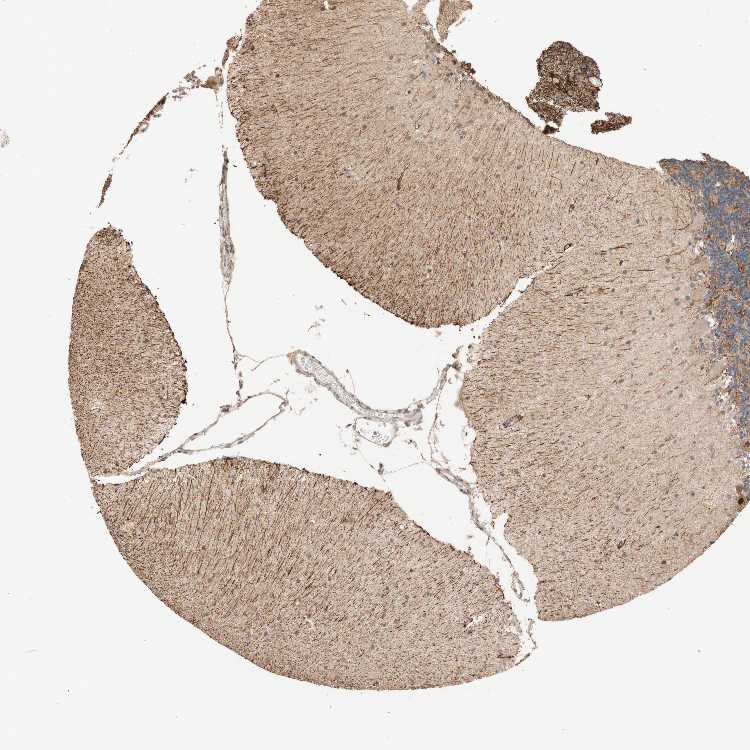

CEREBELLUM - Antibody stainingi

Antibody staining in the annotated cell types in the current human tissue is reported as not detected, low, medium, or high, based on conventional immunohistochemistry profiling in selected tissues. This score is based on the combination of the staining intensity and fraction of stained cells.

Each image is clickable and will lead to virtual microscopy that enables deeper exploration of all samples and also displays staining intensity scores, fraction scores and subcellular localization as well as patient and tissue information for each sample.

Antibody CAB010499

Purkinje cells High

Cells in granular layer Medium

Cells in molecular layer Not detected